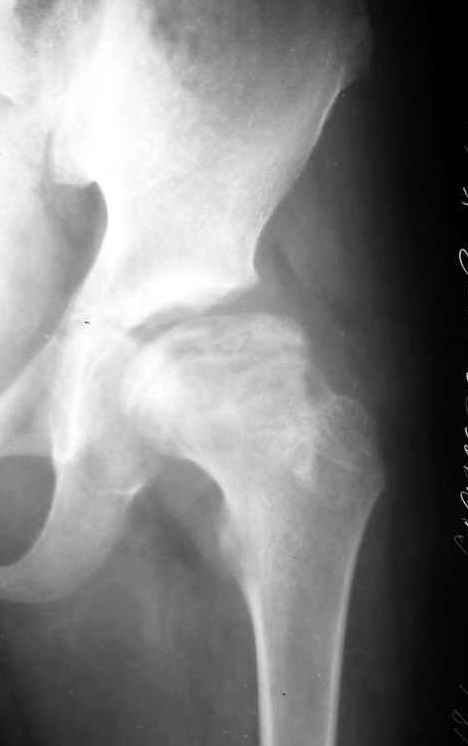

Мальчик 12 лет. Год назад по поводу асептического некроза, в субкапитальную область пересадил аутокостный трансплантат, взятый из Spina iliaca an.sup., на мышечной ножке m.sartorius.

На данный момент движения в суставе в полном объеме и без болезненны, ходит с помощью одного костыля, хотя, может спокойно передвигаться и без дополнительной опоры. Учитывая дисплазию, рекомендовал один костыль пока не бросать. Конечно, чем дольше он будет ходить на костылях, тем лучше для сустава, но ему всего 12, и он как все нормальные дети хочет бегать, прыгать, играть в футбол.Посоветуйте, пожалуйста, как быть?Заранее благодарю, Алишер.

На представленной рентгенограмме (лев. сустав) типичная картина последствия болезни Пертеса с уменьшенной высотой эпифиза. Процесс завершился и нет необходимости в дальнейшем использовании доп. средств опоры. Выраженных дспластических явлений нет. Позвольте пациенту жить без особых ограничений, но ежегодно проводите контрольный осмотр. АИФ.